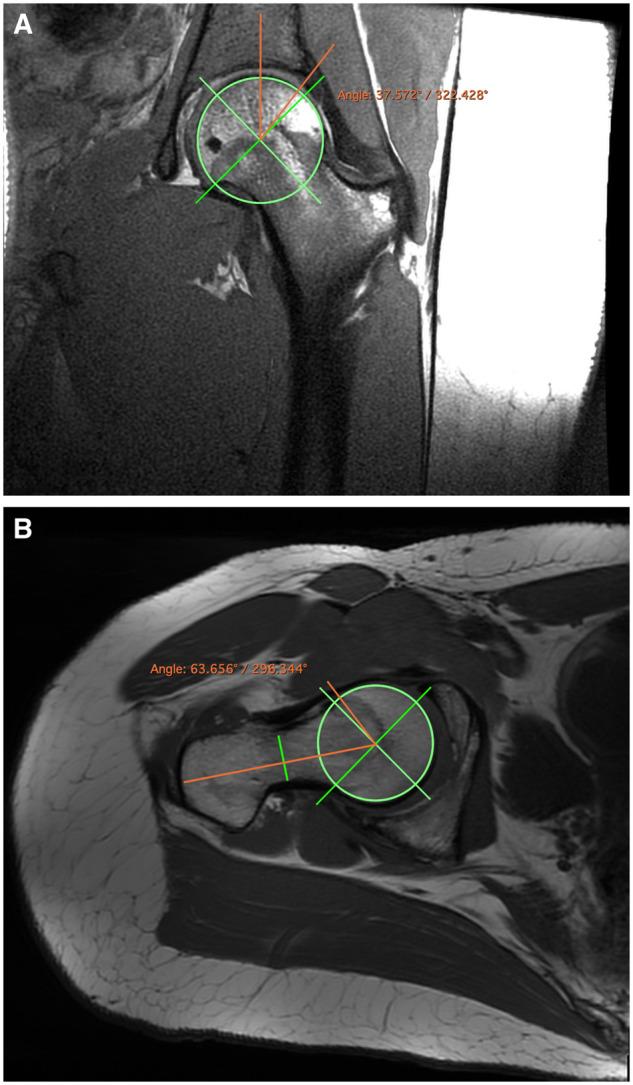

Femoroacetabular impingement (FAI) is a disorder that causes hip pain and disability in young patients, particularly athletes. Increased stress on the hip during development has been associated with increased risk of cam morphology. The specific forces involved are unclear, but may be due to continued rotational motion, like the eggbeater kick. The goal of this prospective cohort study was to use magnetic resonance imaging (MRI) to identify the prevalence of FAI anatomy in athletes who tread water and compare it to the literature on other sports. With university IRB approval, 20 Division 1 water polo players and synchronized swimmers (15 female, 5 male), ages 18-23 years (mean age 20.7 ± 1.4), completed the 33-item International Hip Outcome Tool and underwent non-contrast MRI scans of both hips using a 3 Tesla scanner. Recruitment was based on sport, with both symptomatic and asymptomatic individuals included. Cam and pincer morphology were identified. The Wilcoxon Signed-Rank/Rank Sum tests were used to assess outcomes. Seventy per cent (14/20) of subjects reported pain in their hips yet only 15% (3/20) sought clinical evaluation. Cam morphology was present in 67.5% (27/40) of hips, while 22.5% (9/40) demonstrated pincer morphology. The prevalence of cam morphology in water polo players and synchronized swimmers is greater than that reported for the general population and at a similar level as some other sports. From a clinical perspective, acknowledgment of the high prevalence of cam morphology in water polo players and synchronized swimmers should be considered when these athletes present with hip pain.

股骨髋臼撞击症(FAI)是一种导致年轻患者,尤其是运动员出现髋关节疼痛和功能障碍的病症。发育过程中髋关节承受的压力增加与凸轮形态风险增加有关。具体涉及的力尚不清楚,但可能是由于持续的旋转运动,如打蛋器踢腿动作。这项前瞻性队列研究的目的是使用磁共振成像(MRI)确定踩水运动员中FAI解剖结构的患病率,并将其与其他运动项目的文献进行比较。经大学机构审查委员会批准,20名一级水球运动员和花样游泳运动员(15名女性,5名男性),年龄在18至23岁之间(平均年龄20.7±1.4岁),完成了33项国际髋关节结果工具评估,并使用3特斯拉扫描仪对双侧髋关节进行了非增强MRI扫描。招募基于运动项目,包括有症状和无症状的个体。确定了凸轮和钳夹形态。使用Wilcoxon符号秩/秩和检验来评估结果。70%(14/20)的受试者报告髋关节疼痛,但只有15%(3/20)寻求临床评估。67.5%(27/40)的髋关节存在凸轮形态,而22.5%(9/40)表现为钳夹形态。水球运动员和花样游泳运动员中凸轮形态的患病率高于一般人群的报告患病率,与其他一些运动项目的患病率处于相似水平。从临床角度来看,当这些运动员出现髋关节疼痛时,应考虑到水球运动员和花样游泳运动员中凸轮形态的高患病率。